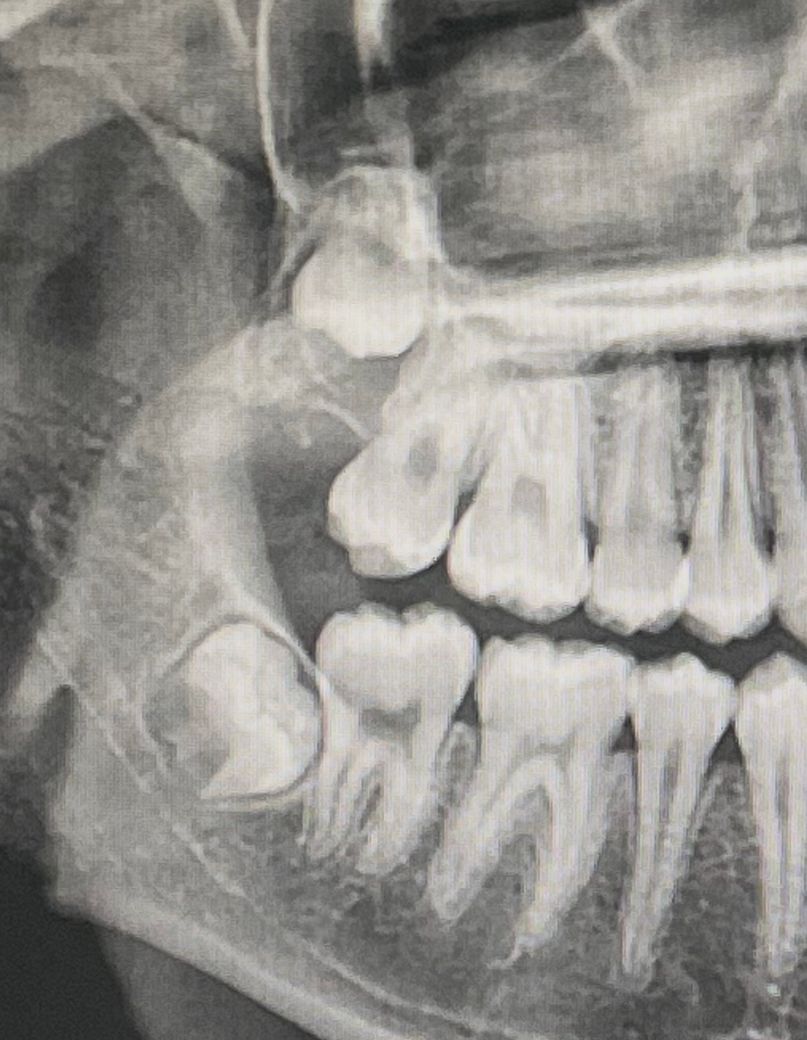

이렇게 되어 있는 사랑니 빼야하나요?

충치나 다른 문제 생긴 적은 없는데 그냥 사랑니 찾아보다가 궁금해져서 물어봅니다. 혹시 추가로 볼이 계속 어금니에 씹히는데 왜 그런건가요?

사진에 보이는 사랑니는 특별한 이유가 없다면 발치를 하지 않으셔도 될것같습니다. 볼살이 튀어나와서 치아에 씹히는거 같으니 음식을 드실때 천천히 드시는게 좋습니다.

1. 결국은 빼주는게 좋을 것 같긴 합니다. 근데 아직 치배 상태의 사랑니고 좀 더 자라고 나서 빼세요

2. 볼을 계속 씹는 건 교합 문제, 치아 각도 문제일 수 있습니다.